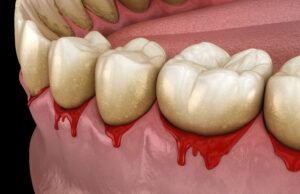

치주질환은 치아에 생긴 끈끈한

치태(플라그)가 제거되지 않고 음식물 찌꺼기가 붙으며

두껍게 치석이 형성되면서 발생하게 됩니다.

치석에 존재하는 세균으로 인해 잇몸이 붓고 피가나며,

심하게 진행되면 치조골이 놓아 치아가 흔들릴 수 도 있어요.